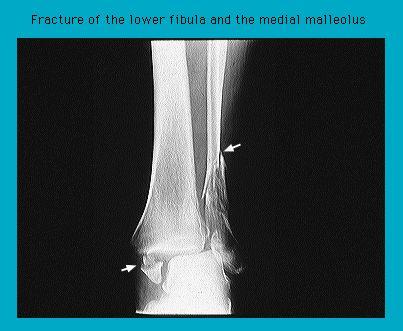

Radiograph showing Pott's fracture of the ankle